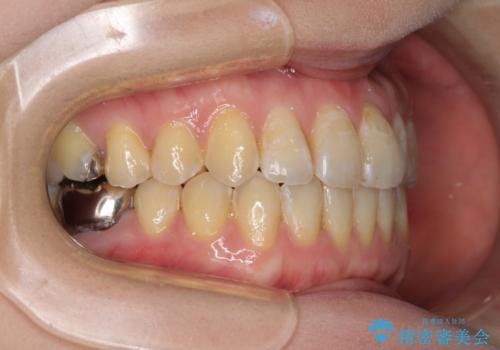

前歯のデコボコを治したい インビザラインによる矯正治療

- 前歯のデコボコを治したいとのことで来院された患者様です。

上下顎ともに歯列全体の後方移動とIPR(歯と歯の間を削る)によってデコボコが解消するように設計し、インビザラインにより治療を行うこととしました。

1日22時間の装着時間をほとんど達成することができず、治療には当初予定の2倍以上の期間を要することとなりました。